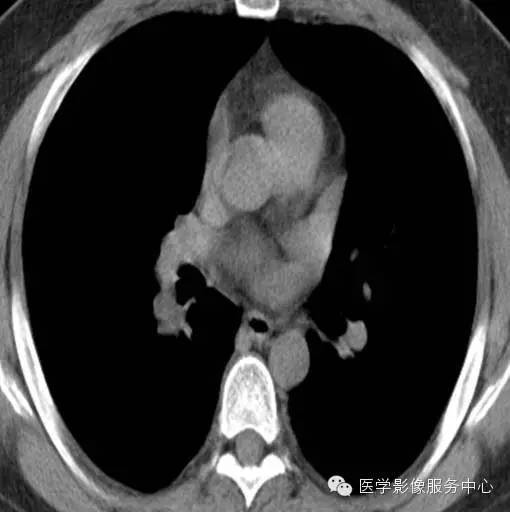

男, 26岁,因“咯血二十余日”入院 。患者一年余前无明显诱因下咯血,鲜红色,自诉无其他不适,至当地医院治疗后缓解,二十余日前无明显诱因下咯血,鲜红色,自诉无伴随症状。

2012年11月22日

影像分析:右侧肺门处见小团块状密度增高影,密度尚均匀,边缘毛糙,增强扫描病灶不均匀强化。

病理:肺神经内分泌瘤